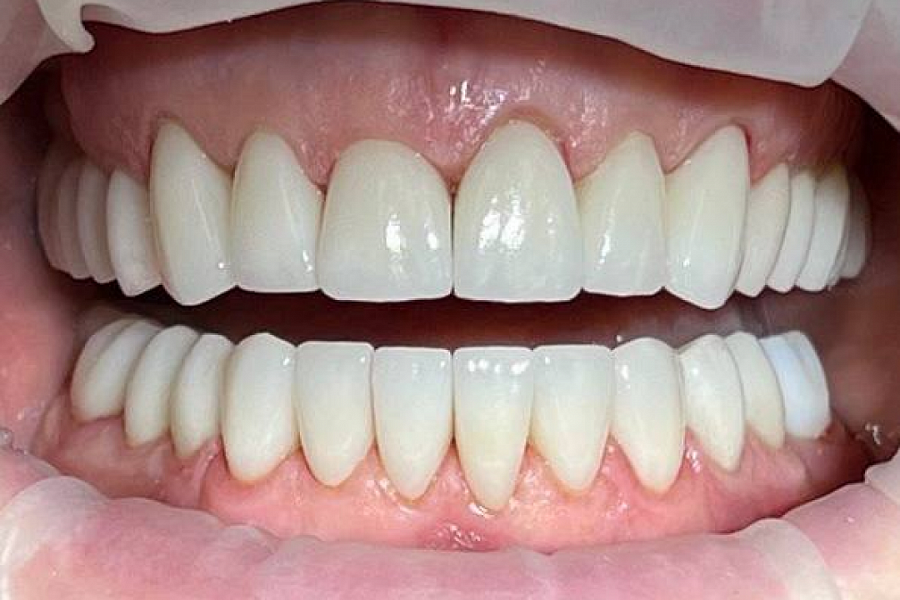

После чего суставы встали в правильное положение, ушел дискомфорт при жевании, а лицо стало более подтянутым (антиэйдж стоматология в действии!)

Пациентка выбрала цвет зубов, который значительно светлее её естественного цвета. Но в результате всё смотрится очень натурально.

Пациентка очень довольна результатом!